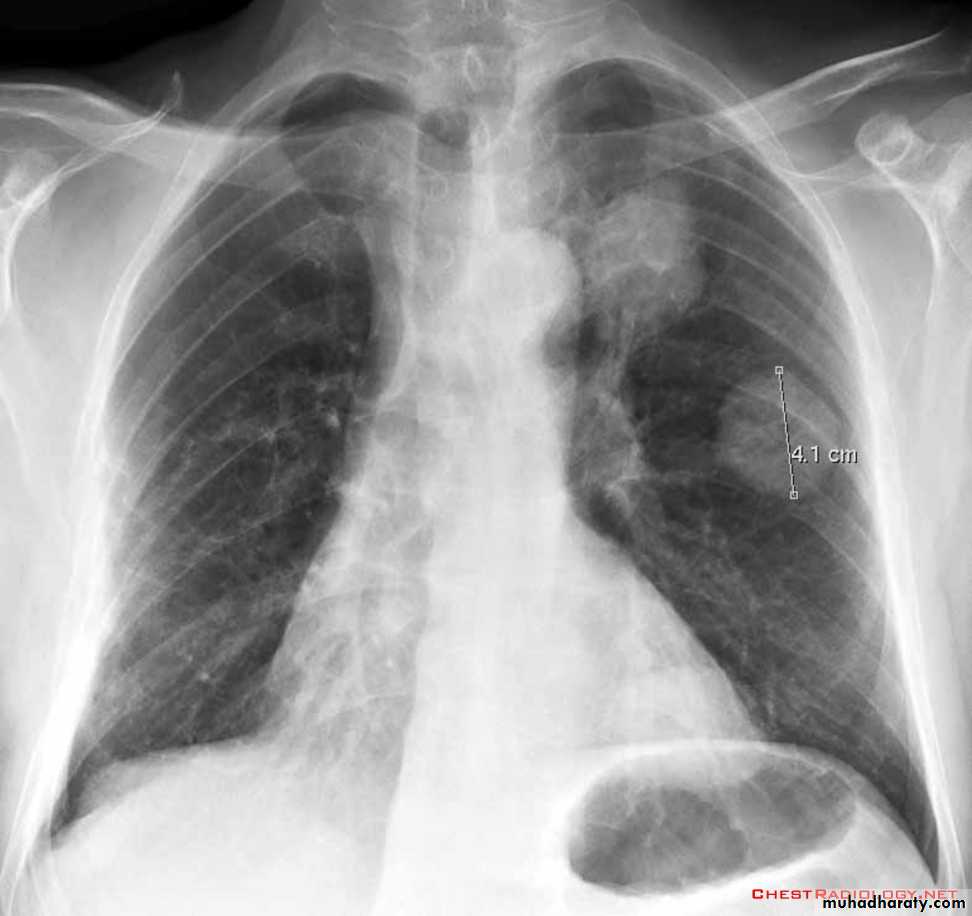

Focal lung diseases-nodule

- mass

Focal ( Solitary or multiple )Diffuse ( alveolar or interstitial )

Well defined margin-Regular- irregular

Size;

5mm-20mm=nodule

>20mm ( 2cm )= mass ( homogenous or complex)

Pulmonary nodule /s1) Bronchogenic CA ( spiculated )

2)Metastasis ( multiple & different size & distribution )

3) Tuberculoma

4) hamartoma

Both are : solitary , peripheral & contain calcification )

5)Hydatid cysts

6)AVM (arterio-venous malformations which show feeding vessels